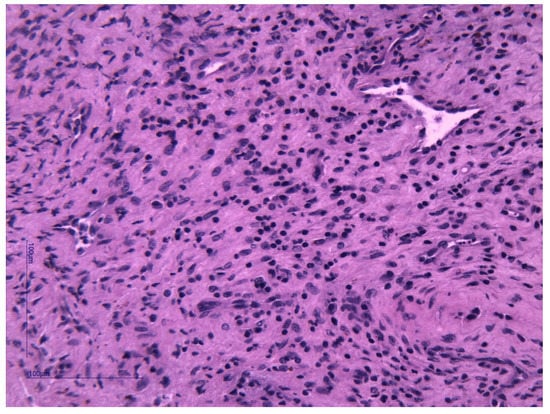

Histopathological examination and immunohistochemistry established the diagnosis of capillary hemangioma with desmoplastic stroma. The pathologist described, on hematoxylin–eosin (HE) staining, tumor proliferation composed of endothelial cells without atypia, forming delicate vascular structures without lumens. The aspect was of a benign vascular proliferation formed by endothelial cells that form fragile submucosal vascular structures; some vessels appeared slightly dilated and with intraluminal red blood cells (Figure 3 and Figure 4). The pathologic assessment did not identify any ulcerations. Immunohistochemical analysis of the tumor showed that it was CD31- and CD34-positive, with Ki67 < 1%. Both immunohistochemical markers CD31 and CD34 are positive in endothelial cells, but CD31 is considered the most dependable endothelial marker [9].

Figure 4. Classic appearance of a capillary hemangioma consisting of delicate vascular structures, some slightly dilated and with intraluminal red blood cells. HE stain, ×400.